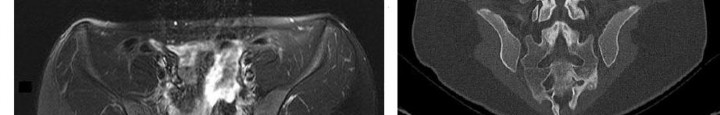

Question 14

A 55-year-old patient with poorly controlled type II diabetes presents with a red, hot, swollen right foot. Inflammatory markers are normal and an MRI confirms no osteomyelitis. Radiographs reveal prominent periarticular osseous debris, fragmentation of the navicular and cuneiforms, and subluxation of the tarsometatarsal joints. According to the Eichenholtz classification of Charcot arthropathy, what stage does this clinical and radiographic picture represent?

Explanation

The Eichenholtz classification describes the natural history of Charcot arthropathy. Stage 0 is the acute inflammatory stage without radiographic changes. Stage I (Development/Fragmentation) is characterized clinically by a hot, swollen foot and radiographically by osteopenia, periarticular fragmentation, bony debris, and subluxation/dislocation. Stage II (Coalescence) shows absorption of fine debris, fusion of larger fragments, and early sclerosis. Stage III (Consolidation) shows remodeling, rounding of bone ends, and stable deformity.